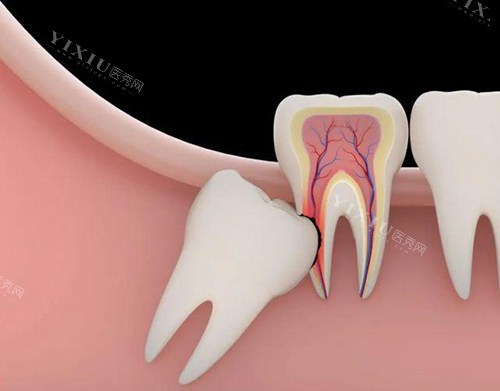

待炎症缓解后,就需要对智齿的去留做出决定了。如果智齿位置比较正,能够正常萌出,并且与邻牙关系良好,不影响咬合功能,那么可以考虑保留。但这种情况相对较少,大多数反复发炎的智齿都需要拔除。拔除智齿是一项小手术,需要到正规的口腔医院进行。

医生会先对口腔进行多方面的检查,包括拍摄X光片,了解智齿的生长情况和周围组织的关系,然后制定合适的拔牙方案。在拔牙过程中,医生会使用局部麻醉,确保患者在拔牙过程中不会感到疼痛。拔牙后,要按照医生的嘱咐做好护理工作,如咬住棉球止血、避免剧烈运动、不要吃辛辣刺激性食物等,以促进伤口的愈合。